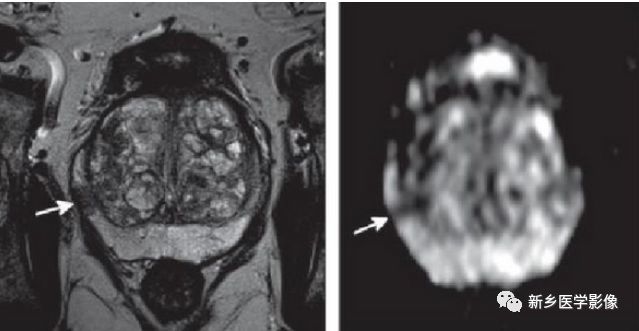

骨髓炎的特殊表现 影像ppt

糖尿病足骨髓炎影像学诊断